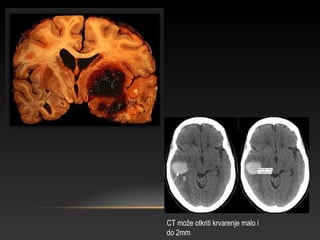

CT može otkriti krvarenje malo i

do 2mm